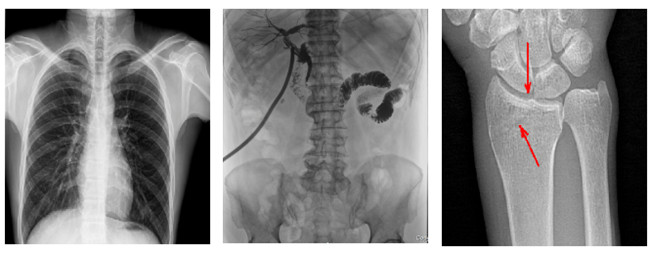

普利德多功能懸吊動(dòng)態(tài)DR,搭載100μm高品質(zhì)動(dòng)態(tài)平板探測(cè)器,不僅滿足常規(guī)的數(shù)字化X線全身攝影需求,同時(shí)還擁有數(shù)字?jǐn)z影、數(shù)字透視、數(shù)字造影、全景拼接等多種功能,極大地拓展了X線檢查在臨床應(yīng)用范圍,為醫(yī)院臨床應(yīng)用帶來(lái)更多實(shí)用價(jià)值。基于百微平板的高清成像,圖像清晰度與分辨率更高,可滿足不同檢查部位對(duì)細(xì)節(jié)成像的高品質(zhì)要求,在胸腹部、脊柱等復(fù)雜骨骼和軟組織的攝片上應(yīng)用,更便于觀察隱匿性病灶,精準(zhǔn)識(shí)別疑難病癥。

不同于靜態(tài)DR拍攝隱匿性病灶時(shí),由于組織重疊病灶難辨,耗費(fèi)時(shí)間更長(zhǎng)且易漏診、誤診,普利德多功能懸吊動(dòng)態(tài)DR可通過(guò)動(dòng)態(tài)實(shí)時(shí)連續(xù)成像,對(duì)于重疊部位病灶或者易被遮擋的病灶進(jìn)行多角度動(dòng)態(tài)觀察,毫秒級(jí)時(shí)間內(nèi)實(shí)現(xiàn)動(dòng)靜態(tài)轉(zhuǎn)換點(diǎn)片,快速、精準(zhǔn)完成攝片。比如隱匿性肋骨骨折,可在透視下觀察患者的呼、吸過(guò)程,避開(kāi)重疊影像,快速點(diǎn)片,保證檢查部位的病癥不被遺漏,實(shí)現(xiàn)精準(zhǔn)診斷。